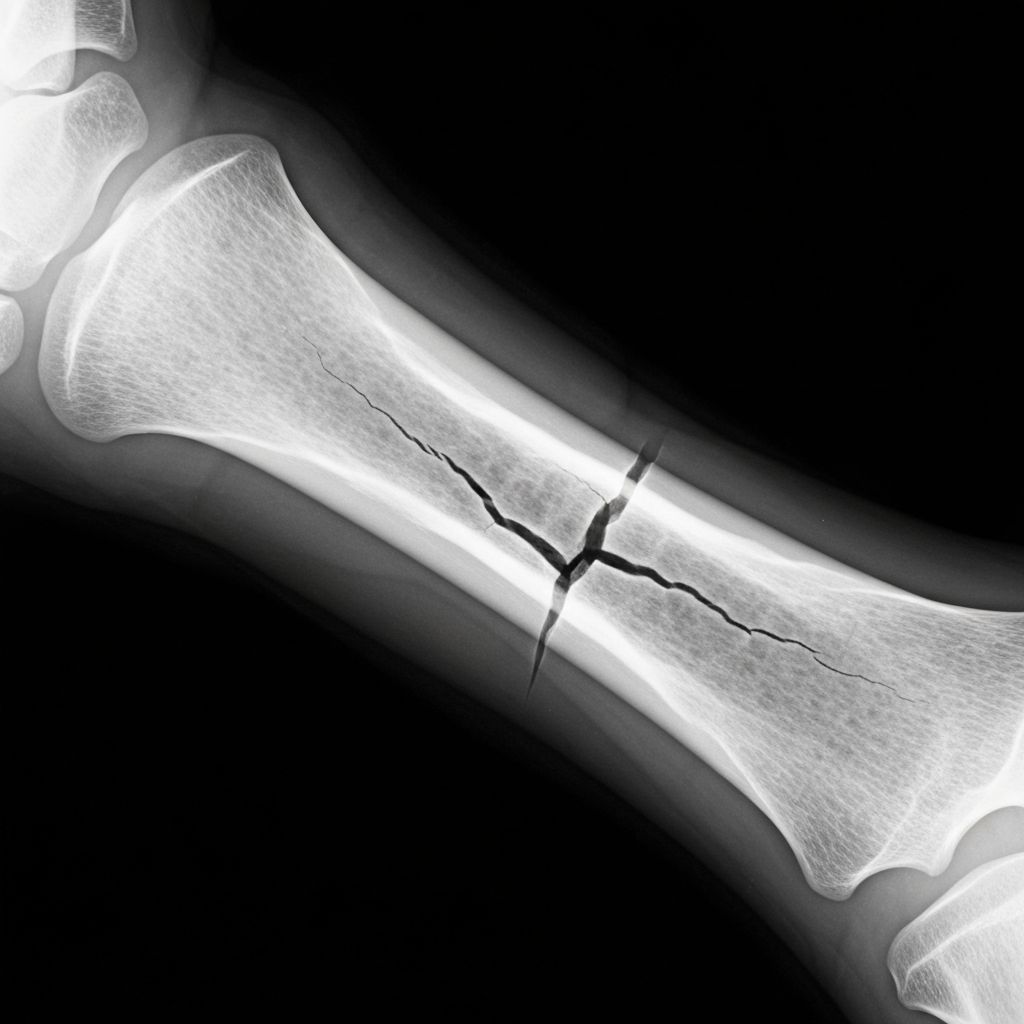

Bone Fractures

Complete guide to fracture types, healing process, and recovery expectations.

Details

Symptoms: Severe pain, swelling, bruising, deformity, inability to bear weight, limited movement

Treatments: Immobilization, casting, surgical fixation, bone grafting for complex cases

Prevention: Calcium-rich diet, vitamin D, fall prevention, protective equipment during sports